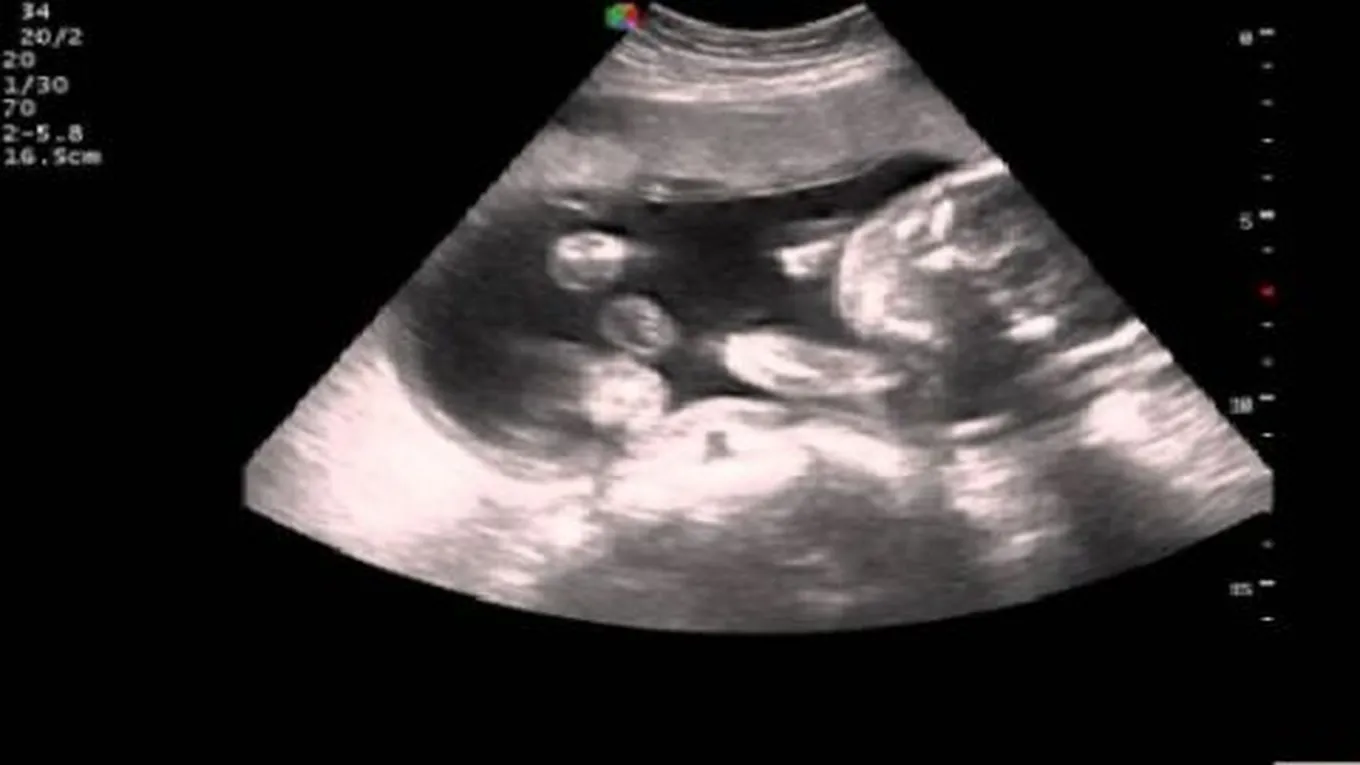

تعتبر حركة الجنين في بطن الأُم من المشاعر الرائعة التي تسعد جميع الأمهات، فهي دليلٌ على أنّ الحياة قد دَبّت في الجنين، وأنه ينمو ويتطور، وقد يرافق مشاعر الفرح هذه بعض مشاعر القلق والتوتر حول طبيعية حركة الجنين وعدد مراتها، وسنحاول من خلال هذه المقال توفير المعلومات اللازمة لكل أم حامل لمعرفة كيف تكون حركة الجنين في الشهر الخامس.

عادةً ما تبدأ حركة الجنين خلال الشهر الرابع من الحمل، إلا أن غالبية الأمهات يشعرن بالحركة مع بداية الشهر الخامس، حيث تستطيع الأم النحيفة، والتي سبق لها وأن حملت من قبل من تمييز حركة الجنين بوقت أبكر من الأمهات ذوات الوزن الزائد، أو اللواتي لم يسبق لهن الحمل، فقد لا تتمكن بعض السيدات من تمييز حركة الطفل، واختلاط الأمر باعتقادها قرصة جوع، أو مجرد تشنجات عضلية، ومن المهم مراجعة الطبيب إذا لم تشعر الأم بحركة الجنين خلال الشهر الخامس للتأكد من عدم وجود أية مشاكل.

عادةً ما تكون بداية حركة الجنين قليلة، ويشعر بها على فترات متباعدة، إلا أنّه ومع مرور الوقت، تبدأ الأم بالشعور بزيادة قوة، وعدد مرات هذه الحركات بسبب نمو الجنين ونمو عضلاته، كما تكون بداية الأمر شبيهة بالحركات البهلوانية، وأحياناً تشبه الركلات التي يكون بعضها قوي وبعضها خفيف، وتصفها بعض الأمهات بأنها تشبه فرقعات الفشار، أو ضربات أجنحة الفراشات.